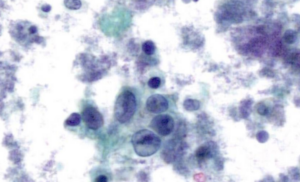

EFCS is pleased to share and invite laboratories across Europe to raise diagnostic standards by participating in the Spanish Society of Cytology’s external quality control program—QPap—combining expert morphological assessment with advanced molecular analysis; ISO 17043 accredited by ENAC, it stands